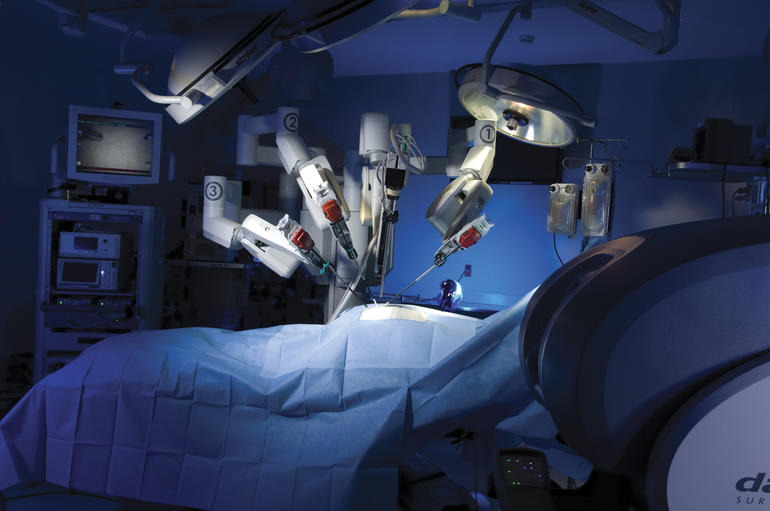

Γι΄ αυτό το λόγο, την τελευταία δεκαετία έχουν επενδυθεί δισεκατομμύρια στα ρομποτικά συστήματα με στόχο τον έλεγχο χειρουργικών μεταβλητών και τη μείωση των τεχνικών σφαλμάτων, τόσο σε σχέση με τη συμβατική μέθοδο όσο και με αυτή της πλοήγησης με ηλεκτρονικό υπολογιστή.

Ωστόσο, παρά την αυξανόμενη χρήση των ρομποτικών συστημάτων για την αρθροπλαστική του γόνατος και όχι μόνο, δεν πρέπει να ξεχνάμε ότι ο πρωταρχικός στόχος για τους γιατρούς και τα σύγχρονα συστήματα περίθαλψης είναι η σχέση παρεχόμενης φροντίδας υγείας που συνδυάζεται με άριστο λειτουργικό αποτέλεσμα αλλά και με το αντίστοιχο κόστος περίθαλψης.

Από τη σχέση χειρουργικής ποιότητας, εγγύησης αποτελέσματος και κόστους, γεννήθηκε στην Ορθοπαιδική Χειρουργική, η MATRIX αρθροπλαστική γόνατος, που χωρίς να είναι τεχνική με βραχίονες ρομπότ, παρουσιάζει εντυπωσιακά κλινικά αποτελέσματα, εφάμιλλα, αν όχι και καλύτερα από τη χρήση των κλασικών ρομπότ, με στατιστικά πολύ μικρότερο κόστος επιβάρυνσης για τον ασθενή, αλλά με άριστο αποτέλεσμα.